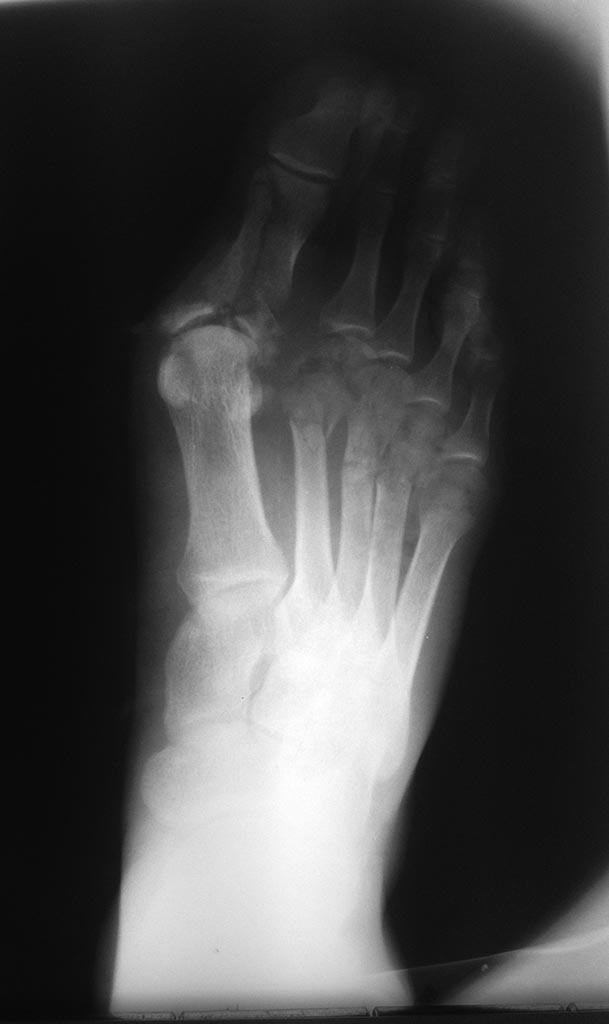

Добрый день!Ситуация неприятная, но не катастрофичная. Лечение потребует несколько этапов. Закрытый остеосинтез головок спицами с подошвенной стороны под контролем ЭОП,I палец потянуть по оси и фиксировать транскутанно спицами 1 мм перпендикулярно плоскости переломов. Сустав скорее всего утрачен, учитывая многофрагментарный характер перелома, но исходно похоже есть плосковальгусная деформация стопы осмотрите внимательно противоположную конечность, сделайте сравнительные снимки, расчертите углы. Вторая проблема заживление мягких тканей отнимет больше времени и сил. Некроз скорее всего будет до сухожилий разгибателей.Вариантов 2 сохранять его как биологическую повязку и уменьшать с периферии - долго, сухожилия все равно оголяться и пластика понадобиться.Либо при явной демаркации некрэктомия, обработка "гидроножем" (есть у Смитов), ВАК и кожная пластика. По сращению переломов и заживлению ран работа с плюснефаланговым суставом. Возможно и не понадобиться.

С уважением Ушаков СА

Здравствуйте. В сложившейся ситуации я бы не заморачивался фиксацией стопы в аппарате или открытой репозицией и фиксацией основной фаланги первого пальца. Все внимание необходимо уделить мягким тканям. По снимкам сложно определить глубину их поражения. Но механизм травмы и то, что мы видим на фотографиях, не дает особых поводов для оптимизма. С целью фиксации пальцев, особенно первого, я бы рекомендовал повязку, обычно накладываемую после реконструктивных операций на переднем отделе стопы. С установкой первого пальца в положение небольшого приведения. Чтобы впоследствии избежать его конфликта со вторым. Такую повязку нужно, по-возможности, менять пореже. И не забывайте о ранней нагрузке на стопу. При хорошей фиксации пальцев повязкой и в послеоперационном ботинке (только без разгрузки переднего отдела, на сплошной подошве) ходьба с нагрузкой до появления болевых ощущений возможна и будет хорошим дополнительным стимулом для заживления, профилактикой регионарного остеопороза и фактором, облегчающим адаптацию к потребующей длительного времени для своего решения проблеме.

А не надо ничего сверхъестественного. Между 1 и 2 пальцами марлевый тампон, костыли, задняя легкая дисциплинирующая лонгетка, гепарин, холод, нпвс. Некроз либо отторгнется корочкой с эпителизацией либо нагноится. Воспринимайте как ожог 3б степени при ведении методом струпа. Недель через 4 нагрузка со стельками с костылями. Срастется раньше, чем заживет.( скорее всего) . И ничего страшного. Терпение...